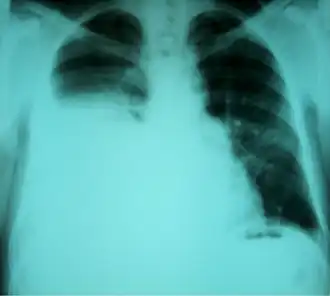

Radiografia torácica mostrando um hidrotórax hepático em uma pessoa com cirrose

Hidrotórax hepático é uma forma rara de derrame pleural que ocorre em pessoas com cirrose hepática. É definido como um derrame de mais de 500 mL em indivíduos com cirrose hepática, não causado por doenças cardíacas, pulmonares ou pleurais. A condição é encontrada em 5–10% das pessoas com cirrose hepática e em 2–3% dos casos de derrames pleurais. Em casos de cirrose hepática descompensada, a prevalência pode chegar a até 90%.[1] Mais de 85% dos casos ocorrem no lado direito, 13% no lado esquerdo e 2% em ambos os lados.[2] Embora seja mais comum em pessoas com ascite grave, também pode ocorrer em indivíduos com ascite leve ou ausente. Os sintomas não são específicos e geralmente envolvem o sistema respiratório.